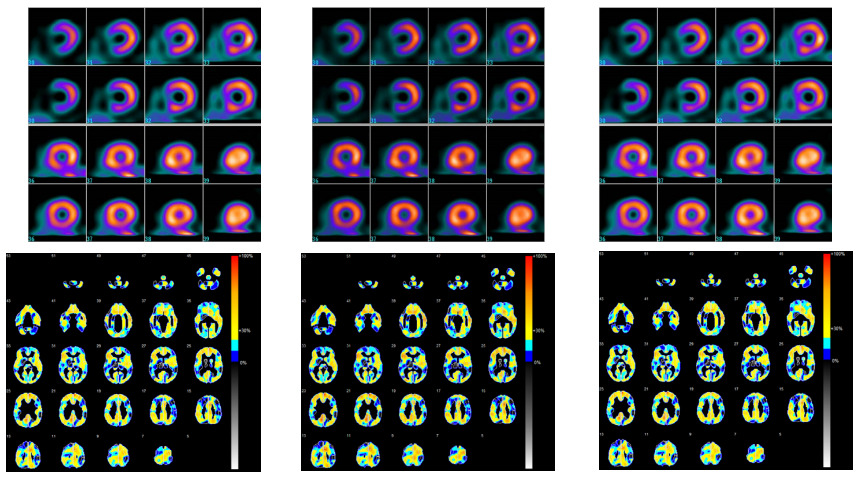

Poniżej zestawiono oceniane obrazy dla porównania:

1) Zgodność ze standardem DICOM część 14 przy odczycie badań monochromatycznych

Rys. 8 pokazuje, że dla 8,5 z 9 monochromatycznych obrazów (ok. 94%) tryb Hybrid Gamma PXL stosujący DICOM GSDF został oceniony na równi z trybem DICOM GSDF, a w jednym przypadku tryb Hybrid Gamma PXL stosujący DICOM GSDF oceniono lepiej niż tryb DICOM GSDF. Nie zdarzyło się natomiast, by tryb DICOM GSDF został oceniony lepiej niż tryb Hybrid Gamma PXL.

Jak wyjaśniono wcześniej, tryb Hybrid Gamma PXL stosuje DICOM GSDF dla wszystkich pikseli monochromatycznych. Wyniki testu potwierdziły, że obrazy monochromatyczne oglądane w trybie Hybrid Gamma PXL wyświetlają się prawidłowo.

2) Skuteczność diagnozy opartej na kolorowych badaniach z krzywą Gamma 2.2

Rys. 10 pokazuje, że dla 31,5 z 86 kolorowych obrazów (ok. 37%) tryb Hybrid Gamma PXL stosujący „mieszaną” krzywą Gamma 2.2 został oceniony lepiej niż tryb krzywej gamma GSDF, a wśród ocenionych w ten sposób badań znalazły się wyłącznie obrazy ES lub RI, bez obrazów US. Nie zdarzyło się, by tryb DICOM GSDF został oceniony lepiej niż tryb Hybrid Gamma stosujący „mieszaną” krzywą Gamma 2.2.

3) Różnice w stosowaniu „mieszanej” krzywej opartej na Gamma 2.2 i prawdziwej krzywej Gamma 2.2

Rys. 11 pokazuje, że dla 66 z 86 kolorowych obrazów (ok. 77%) tryb Hybrid Gamma PXL stosujący „mieszaną” krzywą Gamma 2.2 został oceniony na równi z trybem Gamma 2.2. Z kolei dla 8,5 z 86 kolorowych obrazów (ok. 10%) tryb Hybrid Gamma PXL stosujący „mieszaną” krzywą Gamma 2.2 został oceniony lepiej niż tryb Gamma 2.2.

Stosowanie „mieszanej” krzywej Gamma 2.2 do wyświetlania kolorowych obrazów w żaden sposób nie pogarsza ich jakości.